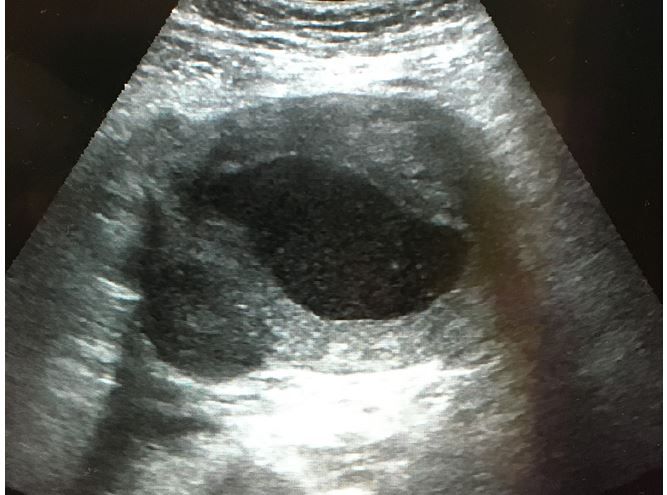

A woman in her 40s is seen in the ED for severe, recurrent pelvic pain. She is s/p endometrial ablation 8 months ago. What does the ultrasound show?

Hematometrium fromThe Emergency Medicine 1-Minute Consult Pocketbook